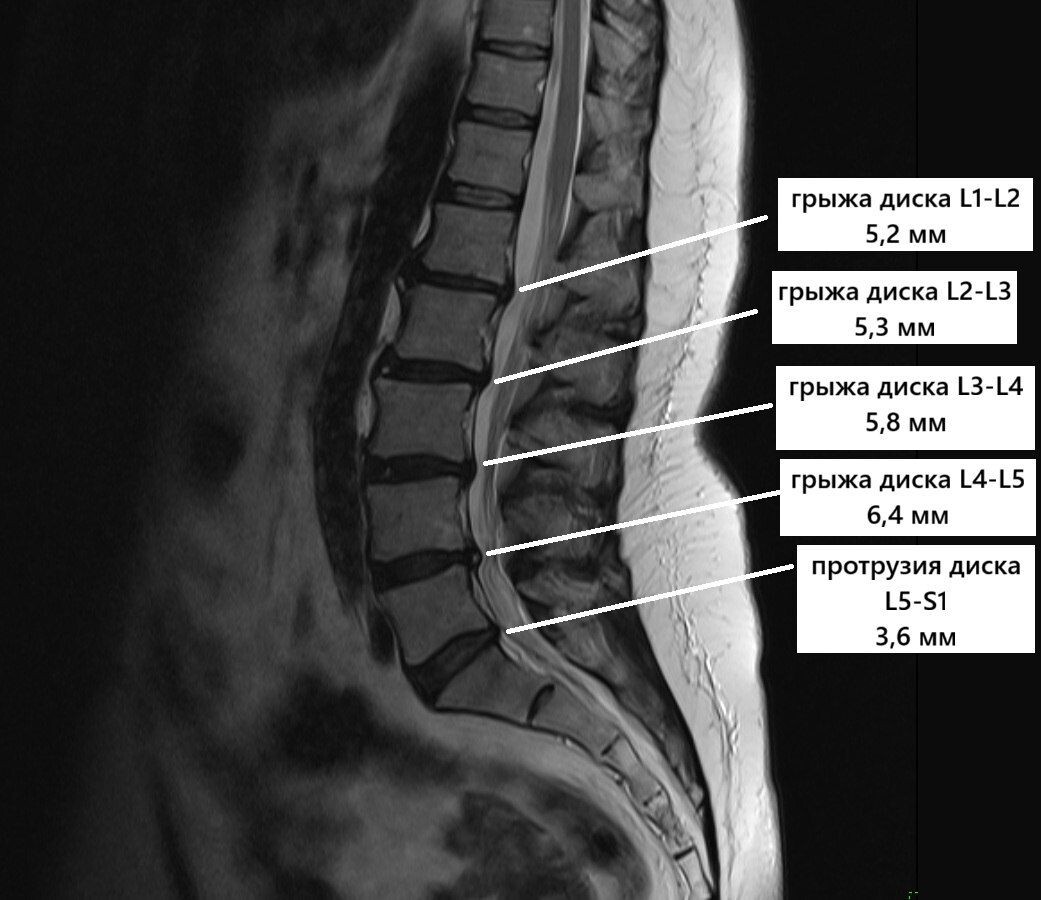

МРТ пациента с множественными крыжами поясничного отдела позвоночника.

Перед вами МРТ-снимок пациента с выраженными изменениями на всех уровнях поясничного отдела.

Разберём основные находки простым языком:

Что обнаружили на снимках:

🔴Между 1-м и 2-м поясничными позвонками - грыжа размером 5,2 мм, расположенная с левой стороны

🔴Между 2-м и 3-м позвонками - грыжа 5,3 мм, которая распространяется в обе стороны

🔴Между 3-м и 4-м позвонками - самая крупная грыжа 5,8 мм, также идущая в обе стороны

🔴Между 4-м и 5-м позвонками - грыжа 6,4 мм смещённая вправо

🔴Между 5-м поясничным и 1-м крестцовым - небольшое выпячивание диска 3,6 мм

Несмотря на множество грыж разного размера, ключевое значение имеет то, как себя чувствует пациент. Отсутствие сильной боли, слабости в ногах и других серьезных симптомов позволяет лечиться консервативными методами.